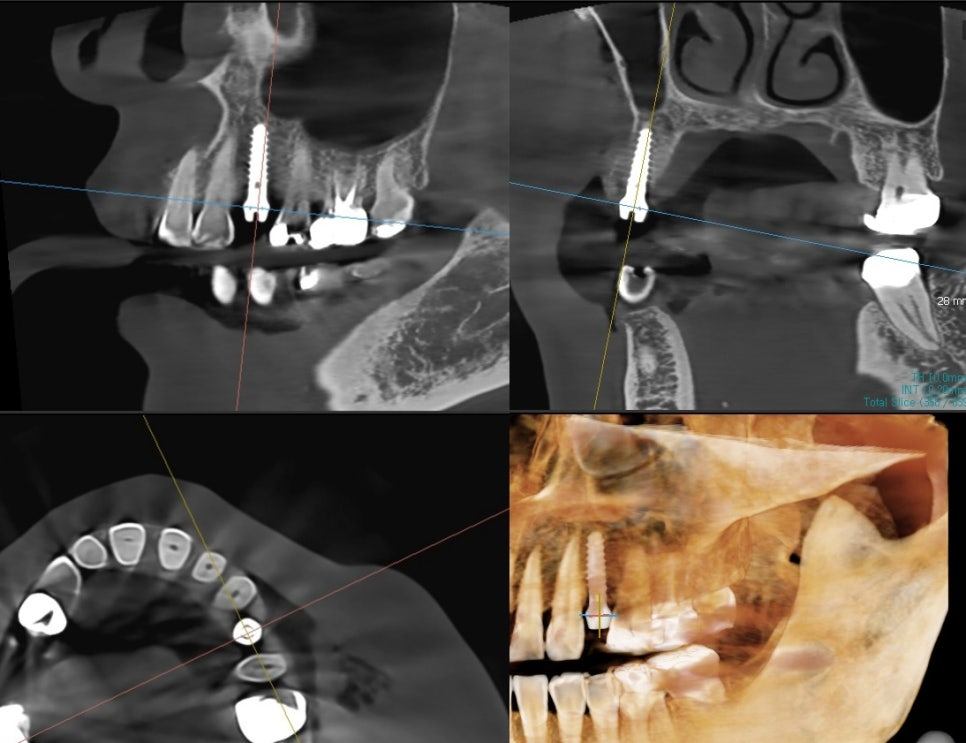

식립 위치에 가이드 핀을 꽂은 상태에서

3D-CT 촬영하여

식립 위치와 기울기를 확인합니다.

아직 발치와의 뼈가

단단히 차지 않은 상태라,

치조골이 약한 쪽으로 핀이 밀린 것으로 확인됩니다.

따라서, CT 상에서 방향을 약간 수정한 뒤

잇몸 절개 없이 핀상방에서

드릴링 하여 정확한 위치에

임플란트 수술을 마칠 수 있습니다.